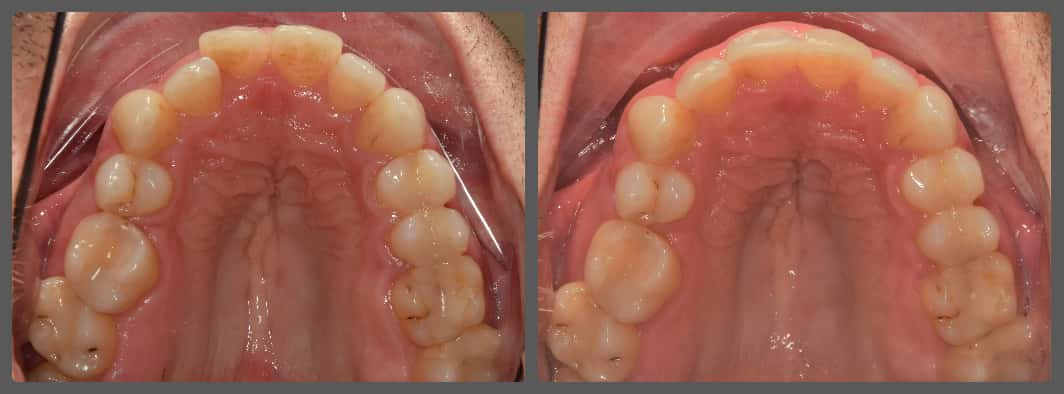

Balázs súlyos alsó torlódása miatt keresett fel magánrendelésemen. A diagnosztikus vizsgálatok során előbbin túl alsó-felső fogívszűkületet, valamint nyitott harapási hajlamot állapítottam meg. Kezelését Pitts21 alsó-felső rögzített fogszabályozó készülékkel kezdtük meg. A nyitott harapási hajlamot a hátsó fogakra helyezett harapásemelővel kontrolláltuk. A torlódott fogaknak tolórugóval és interproximális redukcióval teremtettünk helyet, és intermaxilláris gumihúzással tökéletesítettük a harapást. A fogszabályzó kezelés teljes időtartama alatt Balázs 110%-osan együttműködő volt, ezért 21 hónap alatt sikerült kiemelkedő végeredményt elérnünk.